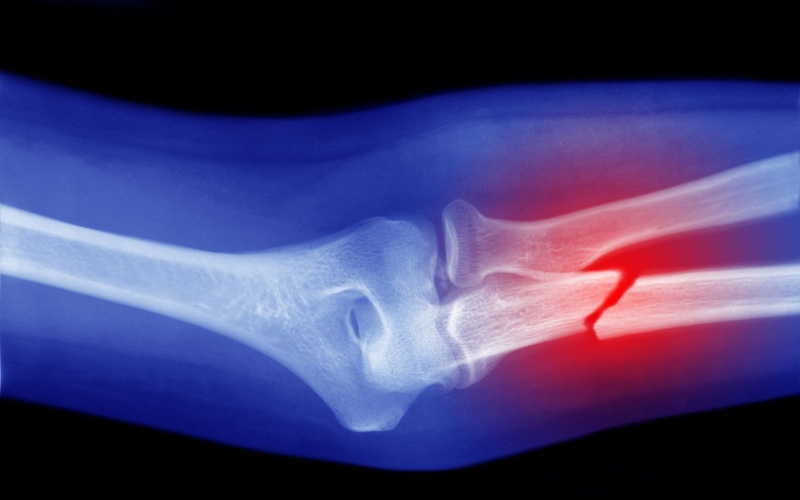

Gãy xương là loại chấn thương rất phổ biến, mất thời gian lâu để phục hồi. Vậy, hãy cùng Nhà thuốc Long Châu tìm hiểu về thời gian lành xương gãy trong bài viết dưới đây nhé!

Xương bị gãy có thể khiến cho người bệnh gặp phải nhiều khó khăn trong sinh hoạt cũng như đời sống hàng ngày. Một trong những vấn đề mà nhiều bệnh nhân quan tâm nhất chính là thời gian liền xương gãy là bao lâu. Quá trình này phụ thuộc vào rất nhiều yếu tố, sẽ được chúng tôi trình bày sau đây.

Khi xương gãy, sẽ dẫn đến sự thay đổi của xương cũng như các phần mềm xung quanh. Những mạch máu nhỏ có thể bị tắc bởi các cục máu đông, bên cạnh đó là thay đổi cấu trúc tủy xương. Những tế bào tủy xương bình thường sẽ chuyển dạng thành tế bào đa hình thái và có xu hướng biến thành tạo cốt bào.

Ở vị trí xương gãy có thể xuất hiện 2 quá trình liền xương, cụ thể là liền xương nguyên phát và liền xương thứ phát.

Khi xương bị gãy sẽ xảy ra tình trạng co mạch giúp hạn chế chảy máu ra từ phần mềm và xương. Khối máu tụ sẽ hình thành ở vùng gãy xương. Trong những khối máu tụ này, nhiều tế bào đa năng có thể biến đổi thành tế bào tạo xương. Một phần đầu xương bị gãy được cố định sẽ xảy ra tình trạng hoại tử do tình trạng thiếu máu nuôi tạm thời khiến cho khe gãy rộng ra. Mô xơ dần hình thành để nối hai đầu xương bị gãy.